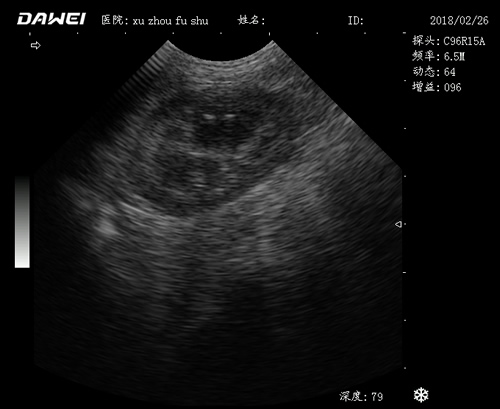

動物寵物超聲診斷儀

適用對象:

牛羊馬豬犬貓及多種家禽、實驗動物、野生動物、及部分水生動物

應用范圍:

·中小動物的肝、膽,脾、腎、膀胱、子宮、妊娠等各組織器官的檢查和病變的診斷